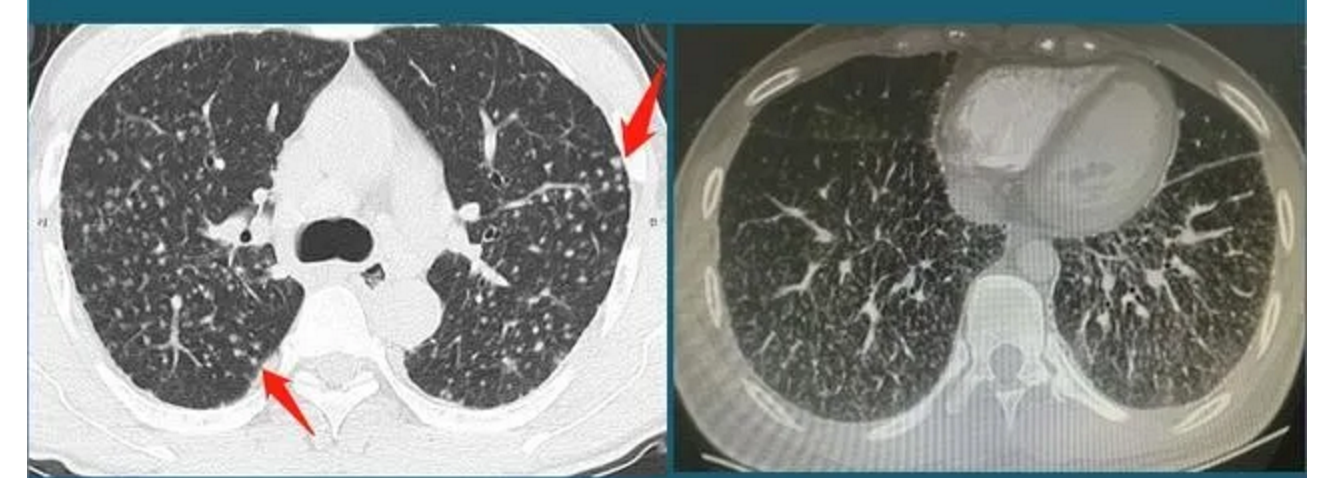

3. 外伤后形成的肺结节

当有巨大外力作用于肺组织时,肺泡会由血液渗出,表现都CT上就像是肺部结节,但这种结节随着损伤的恢复明显缩小或者消失。以下是某患者车祸后胸部CT检查发现的肺结节,红箭头这里的一小片肺组织被车祸撞击暴力撕裂,小血管破裂出血,形成不均匀的高密度影;蓝箭头是气胸和皮下气肿(肺破了,肺里空气溢出到胸腔和肌肉间隙内)。该患者出院时复查胸部CT肺结节已经基本消失。